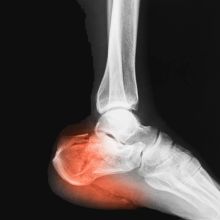

Bolest Achillovy šlachy

Patní ostruha a plantární fascitida